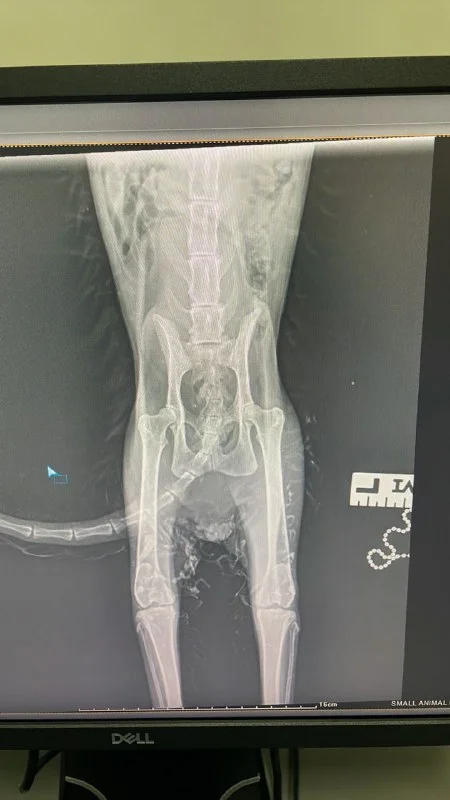

Причину так и не нашли. Снимок не показал трещин или переломов. Кот лапы чувствует и пытается ими двигать. На руках только биопсия

Всем привет. Друзья, не подскажите, пожалуйста, куда можно приютить, с заботой, парализованного кота? Кот бездомный, парализованы задние лапы. Отвез к ветеринару, сделали анализы крови, биопсию (под подбородком с одной стороны что-то похожее на опухоль). Анализы ничего не показали, биопсия показала меньше 50% на злокачественное.